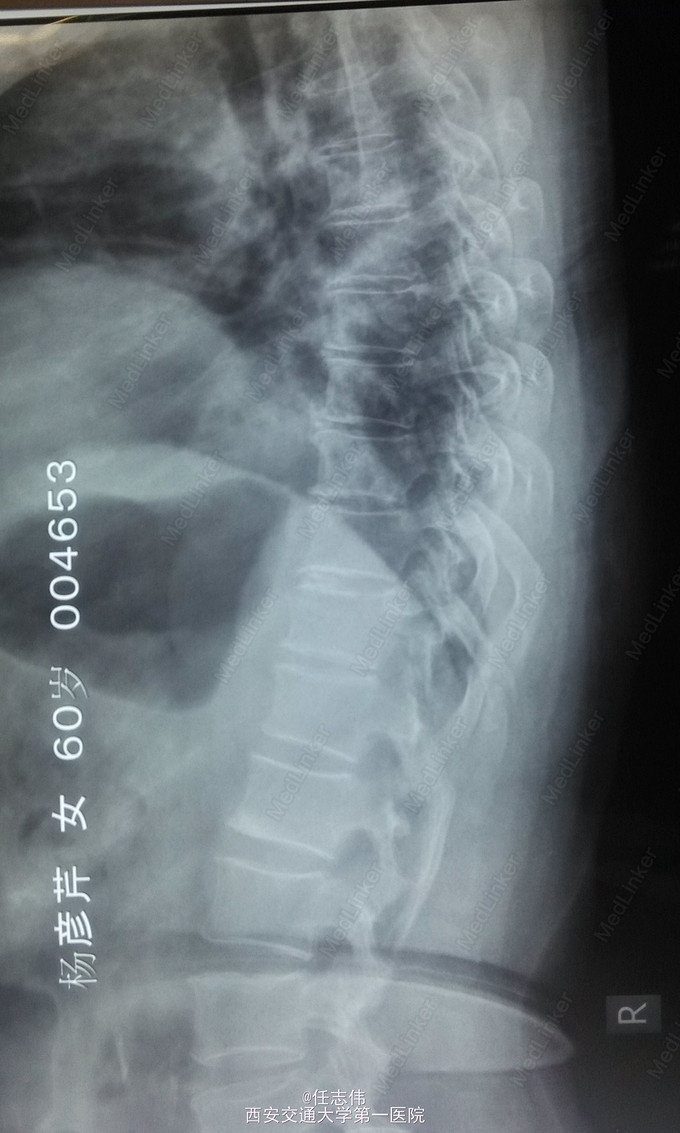

患者女性,60岁,车祸伤致双下肢感觉活动不能8h入院。 8小时前坐农用车时,被横杆撞倒腰部,摔下后感觉胸背部疼痛,双下肢活动不能,伴有短暂昏迷病史。遂来我院就诊。

左侧胸壁广泛压痛,呼吸急促。专科查体:胸背部广泛压痛,自腹股沟平面以下感觉、运动消失,腹壁反射消失,肛门反射消失,巴氏征阴性。双上肢感觉运动正常,骨盆分离挤压试验阴性。

诊断:1.胸11椎体骨折伴截瘫(Frankel A级)2.闭合性胸部损伤,肺挫伤,多发肋骨骨折,双侧胸腔积液 处理:1.急诊入院告病危,心电血氧监护;2.予以甲强龙冲击治疗;3.次日复查胸部CT,查看肺部损伤情况及胸腔积液,后予以右侧放置闭式引流。患者氧合不稳定,2日后复查胸片胸腔积液减少,予以行后路减压内固定融合术。 手术:术中见局部软组织损伤严重,胸11-12棘上、棘间韧带断裂,胸10、11、12双侧关节突有骨折移位,胸11椎板骨折,胸11左侧不能置入椎弓根螺钉,遂行单纯固定。脊髓局部挫伤明显,并有硬膜破损,予以处理。